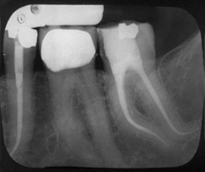

Endodonti (Kanal tedavileri,fiber post uygulamaları)